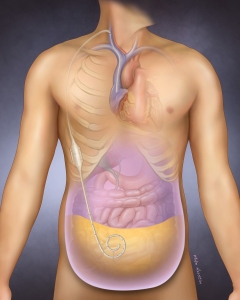

Internal Art Medical Illustration

Blending Art, Anatomy and Science for Creative Visuals

Patient & Professional Marketing

Welcome to my Patient and Professional Marketing page, where I harness the power of anatomical illustrations to educate and empower both patients and medical professionals. My unique approach combines artistry and education to convey complex surgical procedures and the utilization of medical devices in an easily understandable manner.